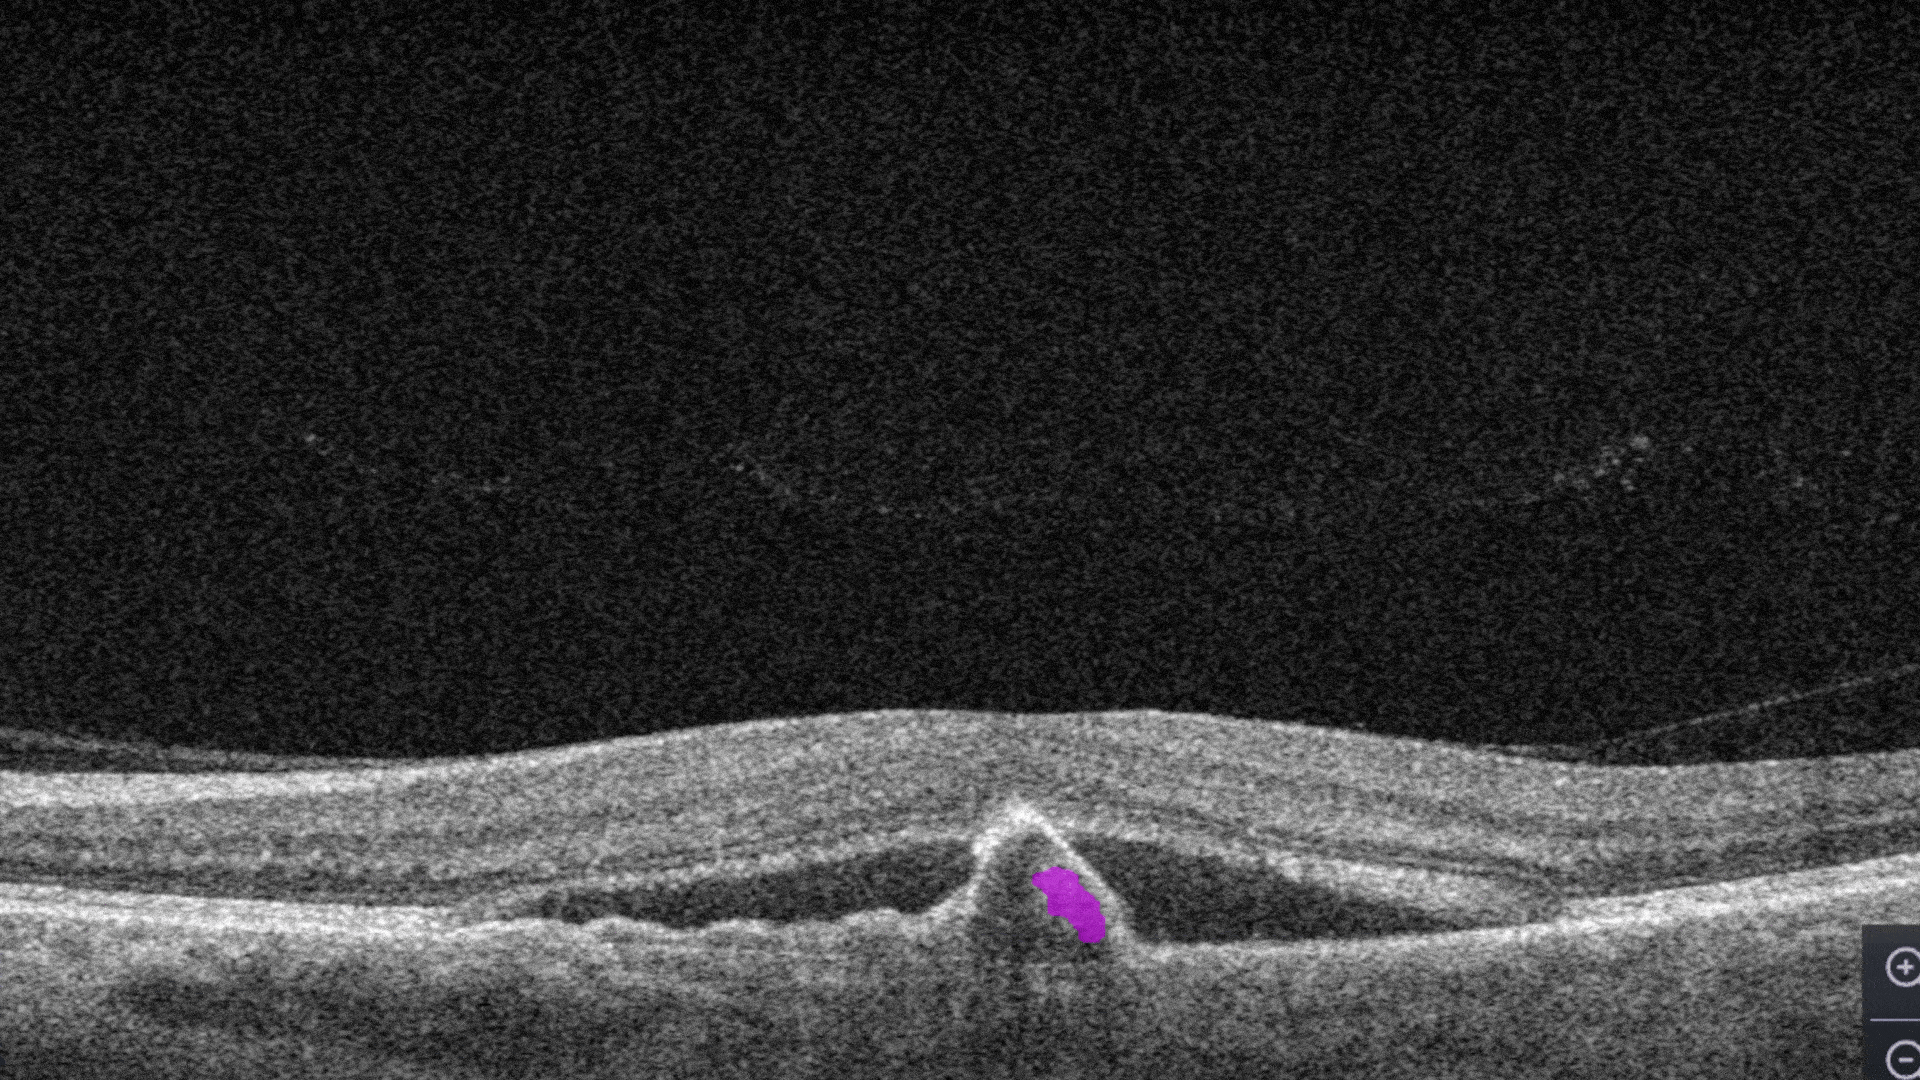

RPE Disruption is the disruption of the Retinal Pigment Epithelium layer

-

Subretinal fluid corresponds to the accumulation of a clear or lipid-rich exudate (serous fluid) in the subretinal space, i.e., between the neurosensory retina (NSR) and the underlying retinal pigment epithelium (RPE), in the absence of retinal breaks, tears, or traction

Fibrovascular RPE detachment. Delamination of the pigment epithelium of the retina is caused by the presence of newly formed vessels (fibrovascular membrane) under the RPE.

Subretinal hyperreflective material (SHRM). It’s a hyperreflective material that is external to the retina and internal to the retinal pigment epithelium (RPE)